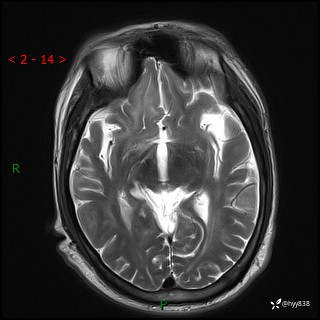

辅助检查:MRI

MRI T2WI